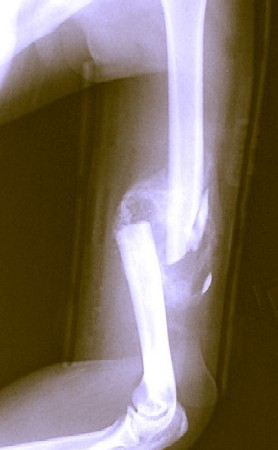

Photo: Bill Rhodes

An X-Ray of a Fracture With Slivers

immediate Remedy be had by removing those [slivers of] Bones"1. Sea surgeon John Atkins agrees. "Any separated Portion of Bone, that we think cannot be replaced and reunited, we must cut and take away"2.